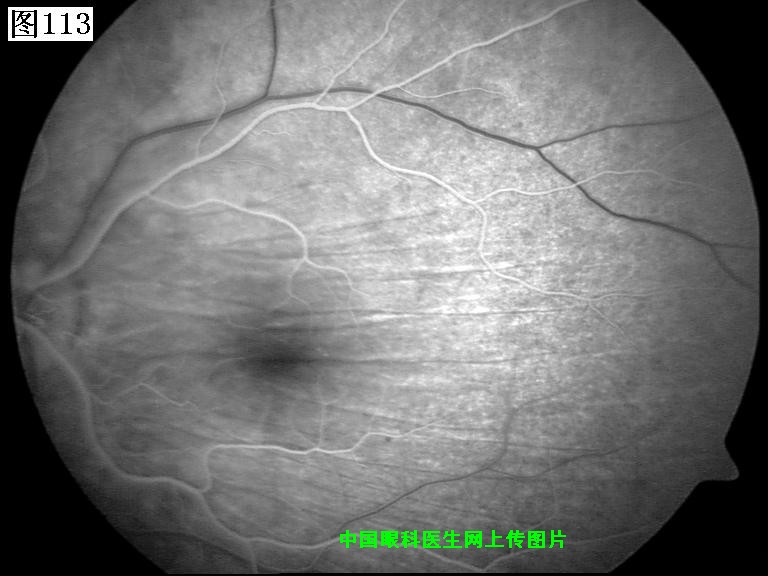

113 114 115 116